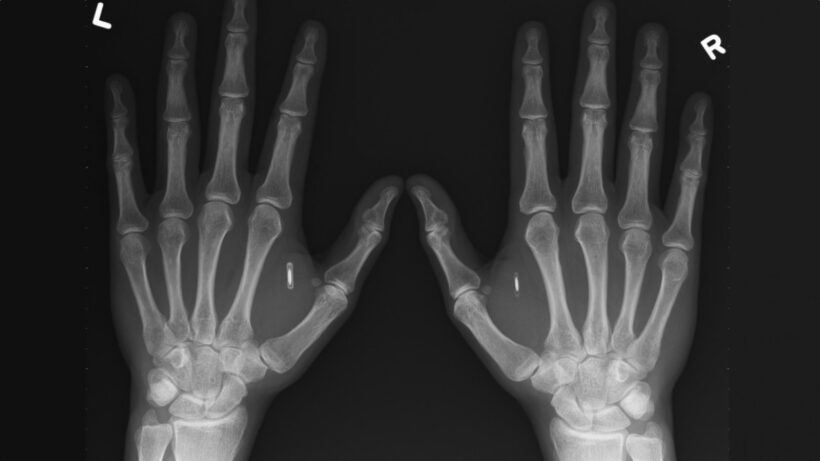

If you believe the headlines, the biohacking – or grinding, or cybernetic enhancement – scene consists of one lone wolf sticking a chip that gets them access to transport systems inside his/her hand every couple of months. Wait a while then the next one comes along, complete with all-caps sensationalism, like clockwork.

This is neatly encapsulated by the experiences of a cyborg I know. Katie Collins, a London-based reporter at CNET, had an NFC microchip, the size of a grain of rice, inserted into her hand at IFA 2015. She did it in the name of intrepid tech journalism, to create a video of the procedure, but also because she’s interested in transhumanism. I asked her how much she uses it these days.

“To be honest, I’ve been quite lazy about testing my chip’s capabilities,” she said. “It’s my party trick – I use it to automatically open the CNET home page when I tap my phone against my hand. The rest of the time it just sits in there dormant, but as new things become possible I may start to use it more and more.”

Hannes Sjoblad, cyborg and one of the founders of the Swedish Biohackers Association, collaborated with the Swedish rail company SJ on a potentially revolutionary project to allow NFC implant payments on its lines. Launched in June of this year, SJ expects only around 200 people to use the method to begin with – it isn’t offering the procedure itself – but Sjoblad says he and his colleagues have chipped over 1,000 people in Stockholm alone in the past year. Often a company will put on the event, then people can choose to swap their work pass for implant access as well as get involved in a spot of “social hacking” to get library, gym or other membership cards added.